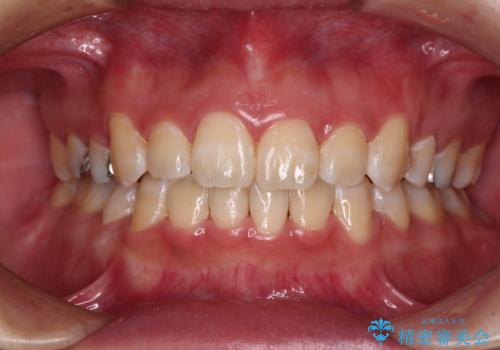

ワイヤーによる抜歯矯正でガタガタの改善